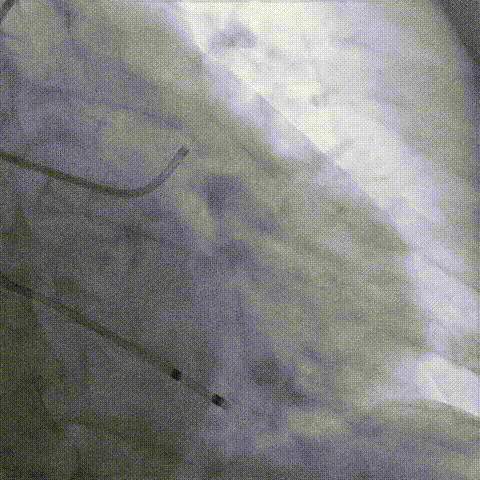

第一次释放

再次评估左冠开口,考虑调整瓣膜深度

回收后调整深度,再次释放

评估左冠开口

左冠开口切线位造影

决定左冠烟囱支架保护冠脉